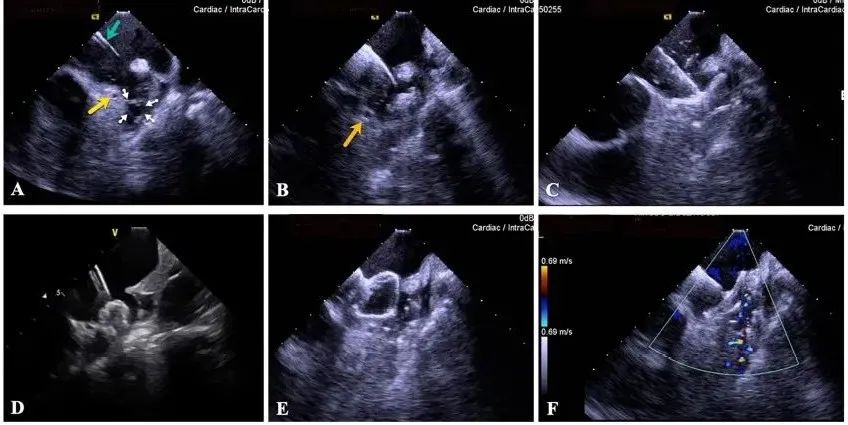

一種與心導(dǎo)管檢查相結(jié)合的超聲心動(dòng)圖診斷新興技術(shù),通過(guò)將超聲探頭置于心腔內(nèi)部,發(fā)射并接收超聲信號(hào),來(lái)精確獲取心臟解剖結(jié)構(gòu)、心臟血流動(dòng)力學(xué)等信息的實(shí)時(shí)成像。與其他影像技術(shù)相比,ICE技術(shù)具有操作簡(jiǎn)單、無(wú)輻射、安全性高、手術(shù)效率高、實(shí)用等優(yōu)勢(shì),ICE在很大程度上有望取代經(jīng)食道超聲心動(dòng)圖(TEE),成為電生理和結(jié)構(gòu)性心臟病領(lǐng)域的理想成像方式。

目前ICE技術(shù)已被應(yīng)用于左心耳封堵、房顫射頻消融、二尖瓣成形、房間隔缺損封堵等多種心臟介入手術(shù),應(yīng)用場(chǎng)景主要圍繞心臟電生理、結(jié)構(gòu)性心臟病等領(lǐng)域,目前以電生理應(yīng)用為主。數(shù)據(jù)顯示,我國(guó)結(jié)構(gòu)性心臟病介入器械市場(chǎng)規(guī)模已從2017年的4億元增長(zhǎng)至2021年的20億元,年復(fù)合增長(zhǎng)率達(dá)48.3%;預(yù)計(jì)到2025年,該市場(chǎng)規(guī)模將達(dá)到104億元,可以預(yù)見(jiàn)ICE市場(chǎng)規(guī)模也將同步高速增長(zhǎng),未來(lái)市場(chǎng)發(fā)展空間廣闊。

心腔內(nèi)超聲(ICE)技術(shù)壁壘極高,國(guó)內(nèi)主要廠商核心部件仍舊為進(jìn)口,集成了超聲和圖像處理最前端技術(shù),包括超聲探頭、線纜、軟件成像算法等,是當(dāng)前內(nèi)窺超聲方向最具挑戰(zhàn)的領(lǐng)域。ICE的應(yīng)用經(jīng)歷了2D平面成像、3D三維立體成像、以及4D的實(shí)時(shí)三維立體成像階段。